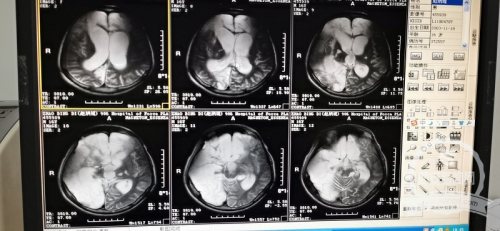

情况比想象的更糟糕,这是接诊的神经外科主任赵永博的第一反应。孩子的整个表现是一个去皮层强直的态势,四肢僵硬的让人担心一不小心会掰折,体温随时会因为肌肉强直收缩超过40℃。看着右侧大脑半球大面积梗塞的片子,相比之前治好过的不少意识障碍患者,这个患儿的治疗难度更大。

高压氧、康复理疗、针灸及药物等综合治疗,情况慢慢有了好转的苗头,患者逐渐开始听着声音转头。赵永博先后和国内多个大医院的昏迷中心进行了远程的会诊和沟通,加上后期的颅骨修补和拔出气管套管,为患儿制定更为合理的治疗方案。